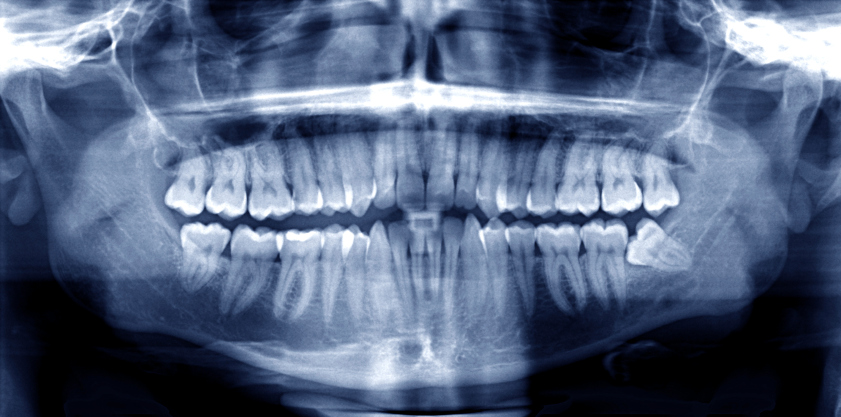

Woman with beautiful smile thanks to houston oral surgeon and dental implantsThe oral surgeons at Piney Point strive to give you the best in oral surgery, and that means we work hard to stay on top of the latest in dental technology. We also like to keep you informed of everything we’re doing to keep your teeth strong and healthy. With that in mind, we’d like to tell you about a new, safer method we have of planning for and placing your dental implants. It’s called the Iluma Cone-Beam CT Scanner, but in simpler terms, it’s a safer, quicker way for us to see an accurate three-dimensional image of your critical anatomy. (Read More)